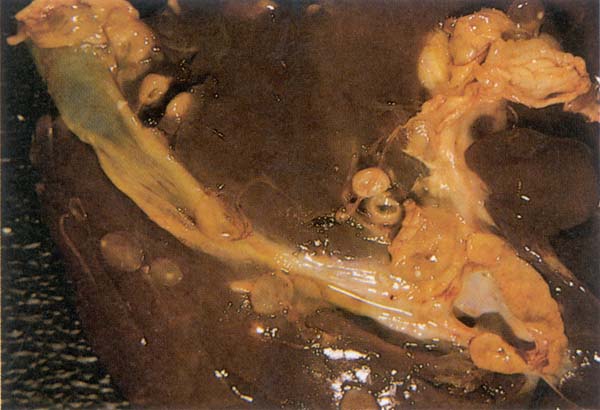

- Fetusta ve hemotoraksta kanamalar (Şekil 150)

Şekil 150 : RVF. Fetusta hemorajiler ve hemotoraks.